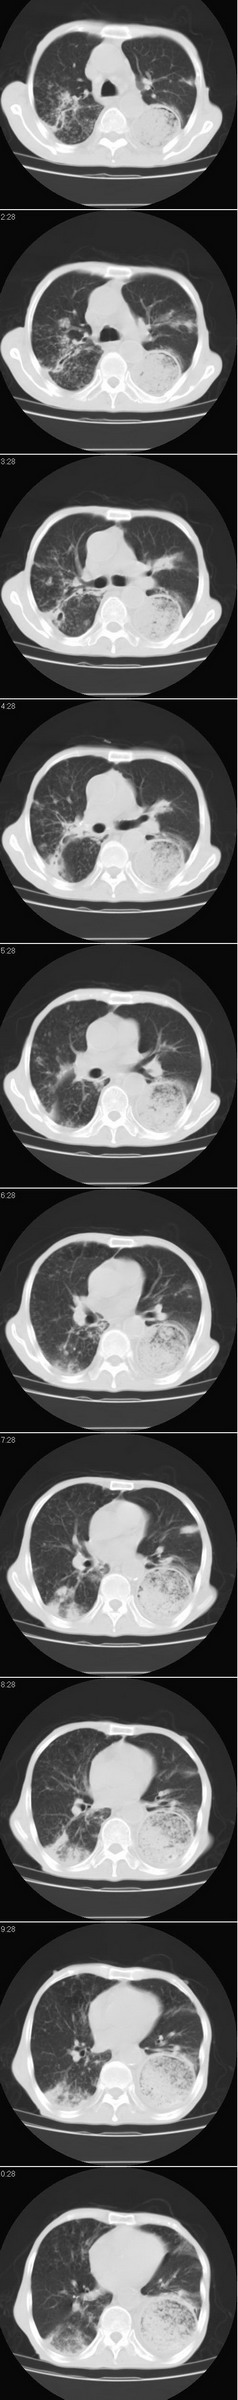

以下是引用dyqct在2007-8-18 14:40:00的发言:[br]考虑:1、食道弓上吻合术后(左侧胸腔胃);[br] 2、右上继发型肺结核;[br] 3、慢性支气管炎合并全小叶型肺气肿、感染。

以下是引用andymaomao在2007-8-18 14:29:00的发言:[br][br]1.该患者应有食道ca手术史,胃位于左侧胸腔(后纵膈旁);[br]2.双肺继发性肺tb?!不排除部分病灶改变为转移灶;[br]3.纵隔气管旁可见肿大淋巴结;[br]4.右下侧后胸壁轻度增厚、粘连。[br]5.另左肺部分肺组织含气不良(受压!?)。[br][br]